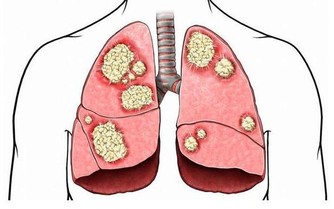

蠕蟲時常會藉由貓狗的排泄物傳染,是一種寄生蟲疾病。

醫生也評斷男子可能是赤腳踩在地板上,才感染到這樣的寄生蟲。